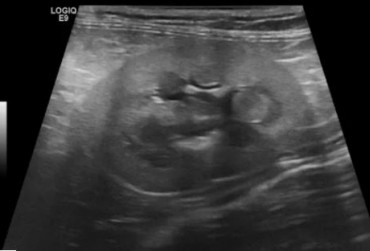

Pies, owczarek szetlandzki 6l. Mukocele. - 2

24 czerwca 2019

Wojciech Atamaniuk

Pies, owczarek szetlandzki 6l. Mukocele. - 1